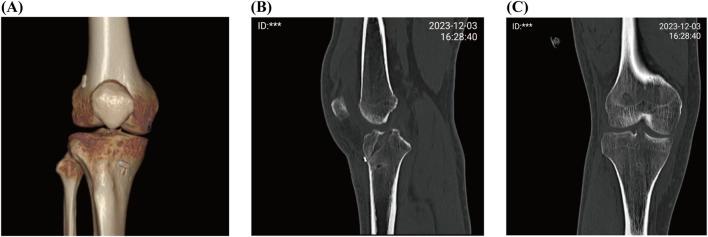

This study included 99 patients with ACL injuries who underwent all-inside arthroscopic ACL reconstruction using either the LARS internal brace ligament combined with hamstring tendon (augmentation group, n = 48) or hamstring tendon alone (hamstring group, n = 51). Postoperative follow-up was conducted using Lysholm, International Knee Documentation Committee (IKDC), Tegner, KOS-ADLS, and ACL-RSI scores to evaluate functional recovery of patients at 1, 3, and 6 months. If necessary, MRI findings obtained at postoperative 3 months were also analyzed to evaluate graft integration and healing dynamics. Tensile strength of the augmented graft was measured through tensile testing. Moreover, to evaluate the postoperative healing status of the augmented tendon, an ACL reconstruction model was established using New Zealand white rabbits. At 4 and 8 weeks postimplantation, rabbit knees were harvested, decalcified, embedded in paraffin, and stained to evaluate new tissue formation. All statistical analyses were conducted using the GraphPad Prism and SPSS software, with appropriate statistical tests applied for comparison between groups.

At 1-month postoperative follow-up, the LARS augmentation group demonstrated significantly higher Lysholm, IKDC, and KOS-ADLS scores than the hamstring group, with P < 0.01 for all comparisons. At 3-month postoperative follow-up, the augmentation group exhibited significantly higher Tegner, Lysholm, IKDC, and KOS-ADLS scores than the hamstring group, with P < 0.05 for all measurements. In the tensile testing, the tendons + LARS and LARS groups showed significantly higher maximum loads and lower elongation than the tendon group with P < 0.001 for maximum load and P < 0.05 for elongation. Examination of the histological sections at 4 and 8 weeks showed that the LARS ligament exhibited excellent biocompatibility, with abundant collagen fibers and neovascularization identified between its fibers.

The combination of LARS internal brace ligaments with autograft tendons in ACL reconstruction provides superior early postoperative outcomes, improving knee stability and patient satisfaction with no remarkable complications. The augmented graft exhibited reliable tensile strength and favorable tissue integration.